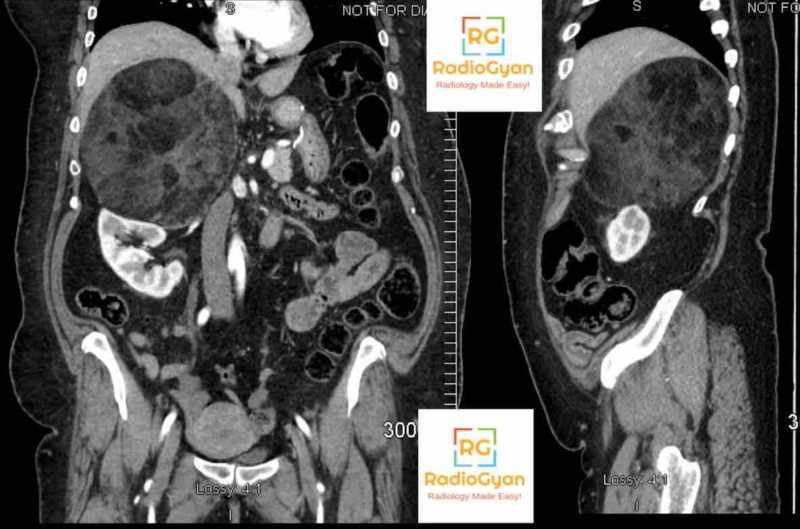

Genitourinary Radiology Cases – Spotter Set 9 Read More ยปGenitourinary Radiology Cases – Spotter Set 9